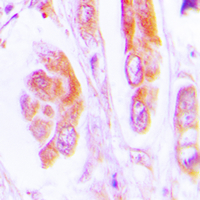

IHC (Immunohiostchemistry)

(Immunohistochemical analysis of Caspase 7 staining in human lung cancer formalin fixed paraffin embedded tissue section. The section was pre-treated using heat mediated antigen retrieval with sodium citrate buffer (pH 6.0). The section was then incubated with the antibody at room temperature and detected using an HRP conjugated compact polymer system. DAB was used as the chromogen. The section was then counterstained with haematoxylin and mounted with DPX.)